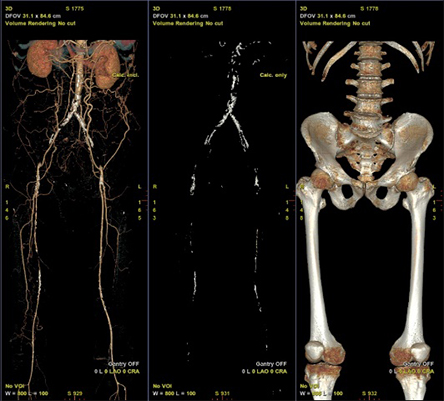

下肢血管における使用例を示す。術前CTAではAortic bifurcationからの完全閉塞となっていた(図5)。完全閉塞部分へのアプローチに対して難渋することが予測されたため、下肢血管解析結果を用いた3D Roadmap使用を検討した。AWVS7は下肢血管解析ソフトを用いることで自動的に血管、骨(術中3D Roadmapの位置合わせ用)を作成する(図6)。狭窄症例などでは自動作成された血管3Dを透視と重ねる3D Roadmapが治療サポートになるが、CTO症例ではワイヤーを進めるためのラインの有用性に着目し、CTO部分を含めた血管センターラインを作成した(図7)。血管センターラインはワイヤーを進める際のReferenceとして有用(図8)であり、3次元での位置情報を有したラインであるため、角度変更やFOV変更、テーブル移動にも追従する。また治療前のDSAでは表示されないTrue面を表示させることは、手技を進めていく中で有用なサポートになったと当院医師よりフィードバックがあった。3D Roadmapは術中にボリュームレンダリングの透過度変更や表示の有無、センターラインの表示の有無も変更可能である。CTO部分を通過させている場合にはセンターラインの表示、通過後のバルーン拡張やステント留置時にセンターラインではなく、ボリュームレンダリング表示による病変部の逆描出など場面に合わせた変更を可能としている。また任意5倍までのデジタルズーム表示機能もあり、今後の症例で使っていきたい。

IGS740_SendaiTokusyukai_06.jpg図6 自動生成された術前CTAの血管、石灰化、骨のVolume